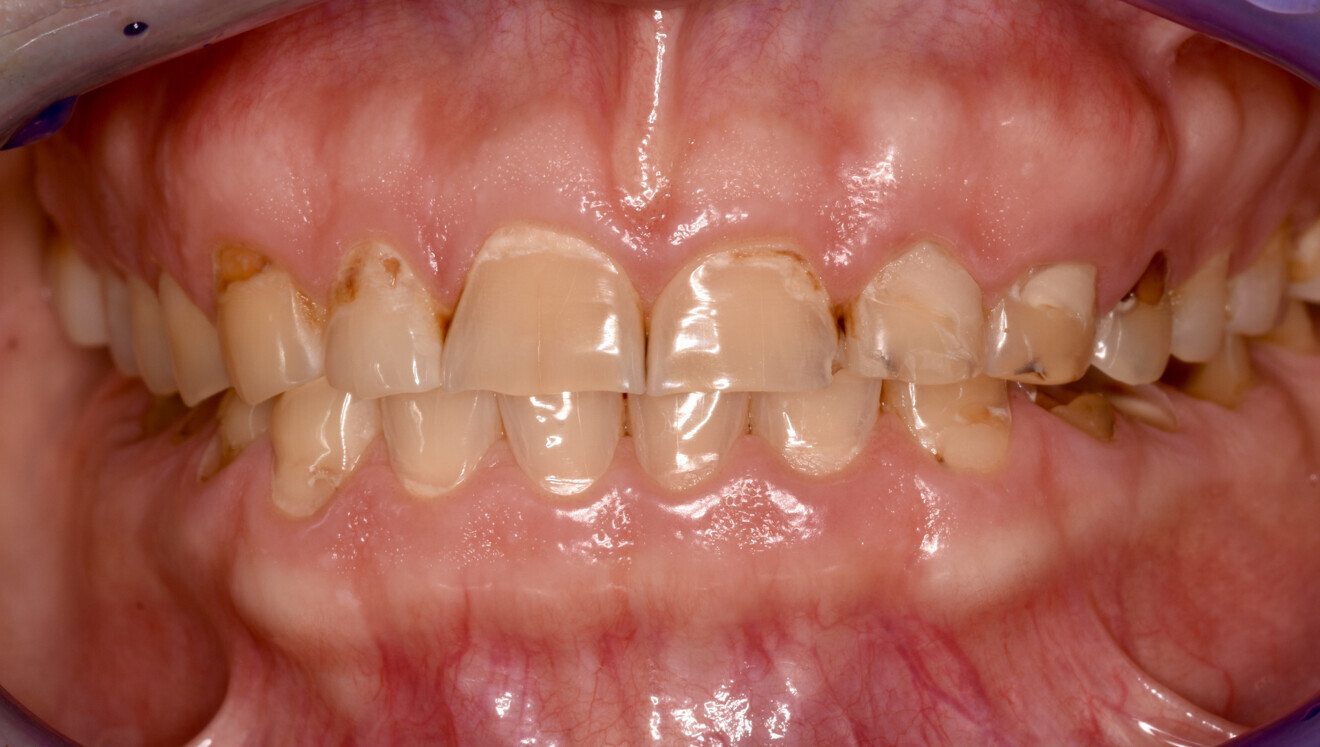

Fig. 1a: Initial situation. Recognisable loss of vertical dimension in the frontal view.

The clinical and radiographic examination revealed pronounced erosive defects on all teeth (Figs. 1a-f). To prevent nocturnal wear of the remaining tooth structure, an occlusal splint had been prepared by the patient’s general dentist in the past. Quick screening for temporomandibular disorder using the tool developed by the German Society of Craniomandibular Function and Disorders was carried out and revealed no functional abnormalities. The diagnosis was generalised, highly pronounced erosion due to exogenous acid (cola), abrasion and attrition with decreased OVD, multiple carious lesions, dentine hypersensitivity, gingivitis and compromised aesthetics.